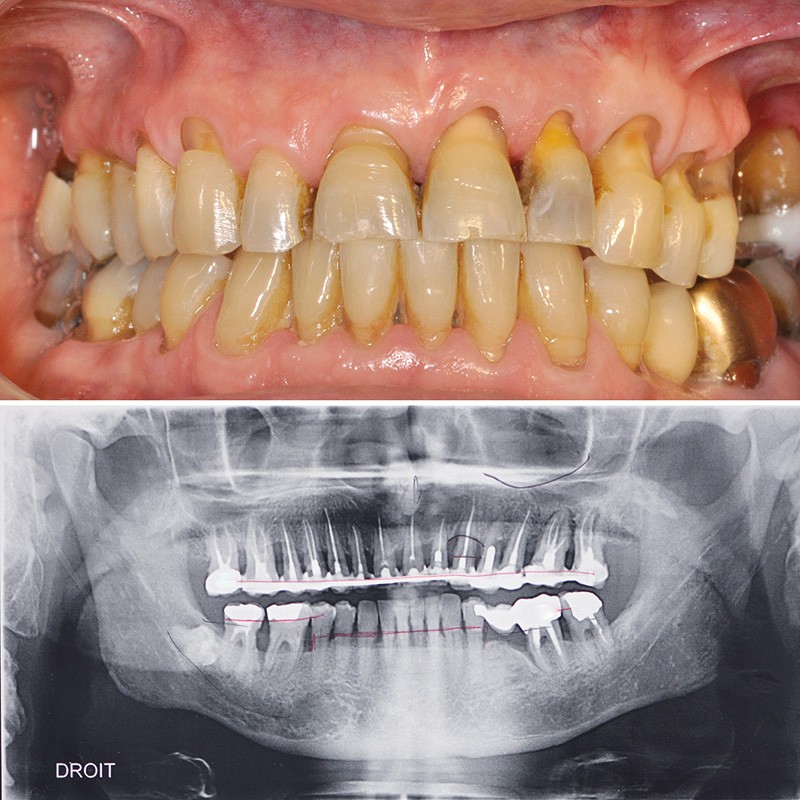

Ainsi, chez ce patient (fig. 3) quelle(s) solution(s) thérapeutique(s) peut-on envisager pour répondre au problème de mobilité dentaire en respectant son souhait de conservation ? Doit-on envisager d’extraire toutes les dents et d’avoir recours à une solution implantaire ou existe-t-il une solution fiable de conserver ses dents ?